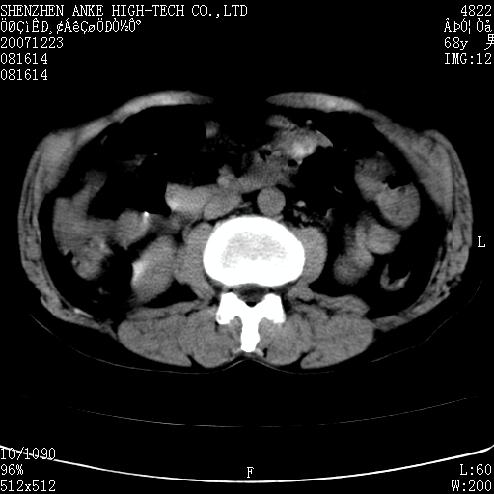

患者:男,63岁,2年前胆囊切除术后,现右上腹部剧烈疼痛近2天.

肠管积气明显.

肠道准备不好,干扰影大。

肠道气体伪影干扰太大了,应该是干扰所致,未见明显异常。

肠道准备不好,胃底后壁显示不清,右肾改变考虑为伪影。

上腹部ct平扫未见明显异常。(肠道气体较多,患者呼吸了)